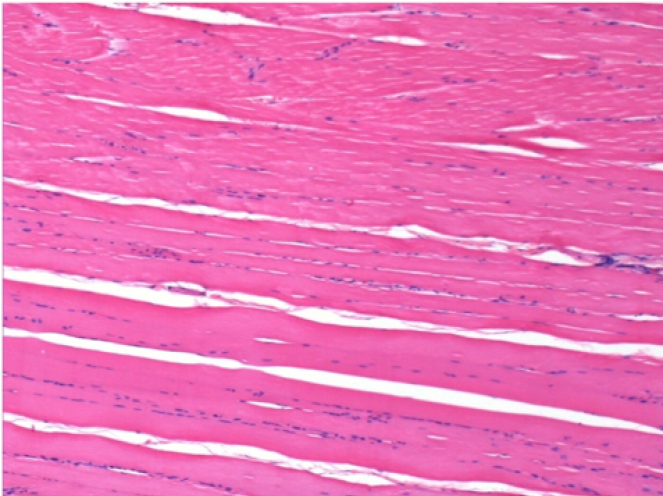

Через 1 місяць після ін'єкції Ендопілу 0,1 мл у правий претибіальний м'яз.

Те, що видно на знімках чорним кольором, не є некрозом, як можуть собі уявити деякі науковці!

Насправді, слід взяти до уваги 4 висновки

Через 3 місяці (90 днів) після ін'єкції Ендопіл 0,1 мл в правий претибіальний м'яз.